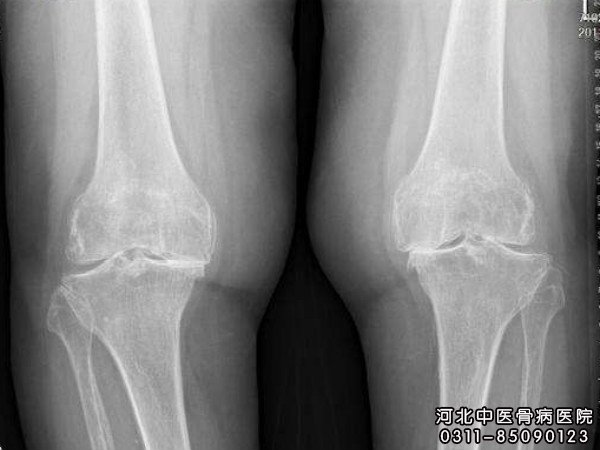

专家表示,膝关节结核的发病率也在逐步升高,同时很多患者也在找相关的治疗方法,那么膝关节手术怎样进行治疗?接下来我们就来看看吧。

膝关节结核的手术疗法

对单纯滑膜结核的患者多行滑膜切除术,术后用托马斯架行皮牵引6—8周,并在牵引下练习关节活动。10岁以内小儿全关节结核病变较轻的常行病灶消除术,术后皮牵引6—8周,以后进行功能锻炼,下地时患肢不负重,术后6个月患破可负至步行。15岁以上全关节结核中患者常行膝关节加压融合术、用膝关节加压器固定,以促进骨愈合,外用长腿石膏托固定。

膝关节结核护理时须注意保护两根固定钢刽不要触碰,以免引起疼痛。4—6周取下加压融合器,换成石膏管型,下地练习步行,患肢不负重。直至x线证实有骨愈合。要认真进行车引,注意石膏的护理和患者的全身护理。